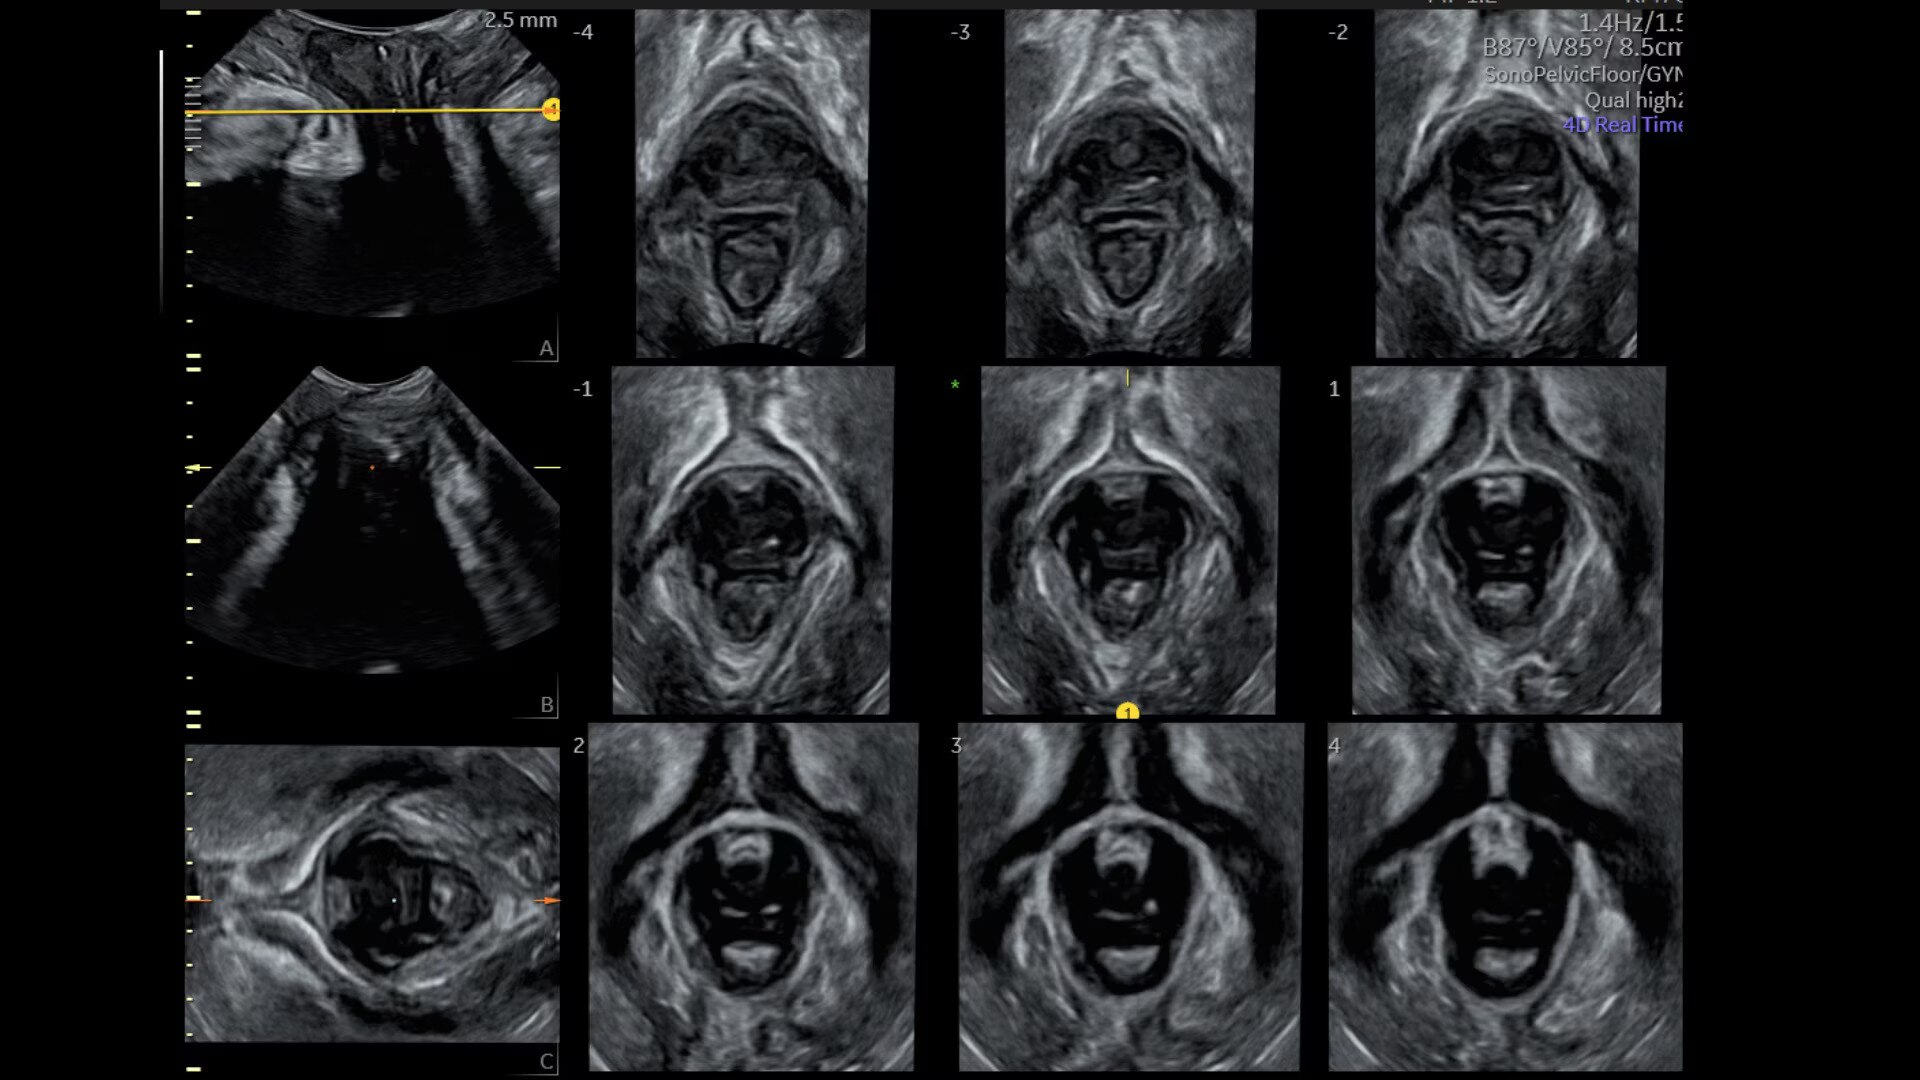

Assess pelvic floor anatomy using guided workflow & AI

Using a guided workflow and AI, SonoPelvicFloor:

• removed exam complexity by automating plane alignment and measurements

• can reduce keystrokes by up to 75% and offer users a time savings of up to 80%